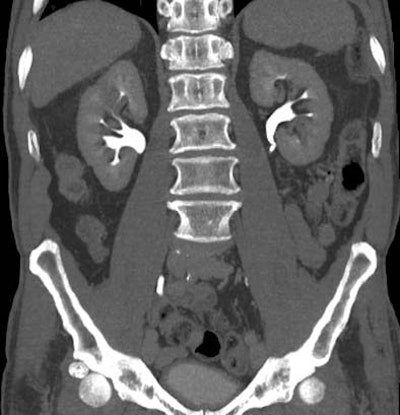

| Transitional cell cancer of the right upper ureter. Above, axial excretory-phase CT showing soft-tissue filling defect in the upper third of the ureter. Below, coronal thin-slab maximum intensity projection showing characteristic signs of ureteral transitional cell carcinoma. Images courtesy of Dr. Nigel Cowan. |